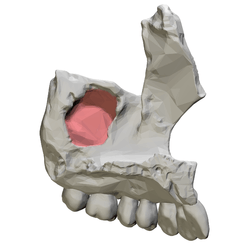

![]() Left maxilla, medial view. Maxillary sinus shown in red. | |

Animation. Maxillary sinus shown in red.

Maxilla shown in semi-transparent. Maxillary sinus shown in red.- Right maxilla. Medial view.